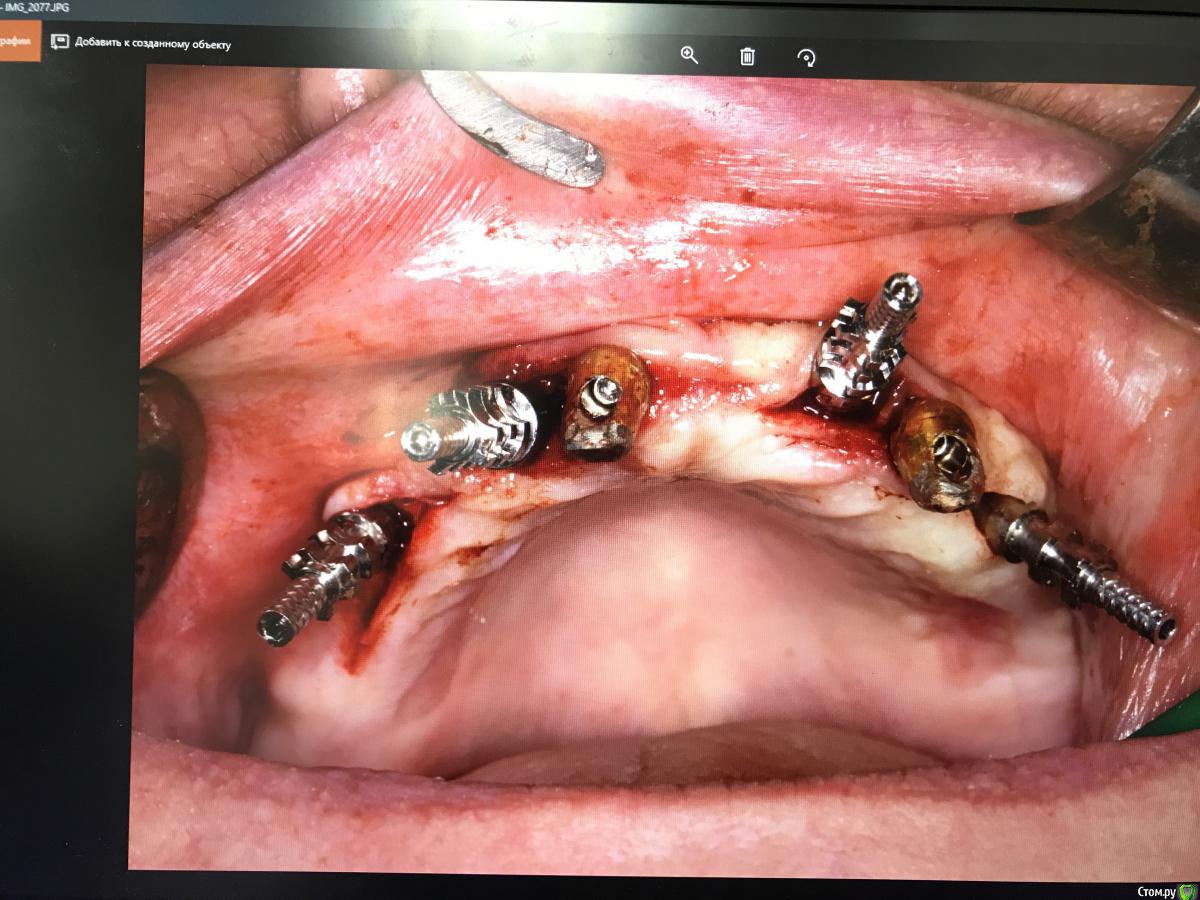

ksenistom Опубликовано 20 июня, 2018 Поделиться Опубликовано 20 июня, 2018 Добрый день,доктора посоветуйте пожалуйста конструкцию,система дентиум. На верхней челюсти установлены временные имплантаты в области 1.3; 2.3;,на нижней челюсти в области 3.1;4.6; 3.6 - оставлен для временной опоры протеза. Была проведена подсадка костного материала,в области установленных имплантатов.Рассматриваю два варианта: 1) установить балку,но с учетом,мягко говоря,«завала» осей имплантатов,придётся использовать мультиюниты,которые увеличат высоту прикуса и смущает распределение нагрузки балочной конструкции,с учётом положения наклона имплантатов.2) протезирование на локаторах???Посоветуйте,что делать в данном случае? Ссылка на комментарий

korotkevich Опубликовано 21 июня, 2018 Поделиться Опубликовано 21 июня, 2018 здесь только мультиюниты Ссылка на комментарий

Amigo43 Опубликовано 22 июня, 2018 Поделиться Опубликовано 22 июня, 2018 Что за постановка крестом? Ссылка на комментарий

AndyAndy Опубликовано 22 июня, 2018 Поделиться Опубликовано 22 июня, 2018 Что за постановка крестом?Работа выполнена в стиле «когда кость диктует условия» Ссылка на комментарий

Dman Опубликовано 25 июня, 2018 Поделиться Опубликовано 25 июня, 2018 ****** это просто ******* ***** по делу наверху: если временные импланты интегрированы, то выкрутил бы передние постоянные запротезировал бы. с низом нужно разбираться, какой-то из имплантов точно не в кости - нужно сделать кт или пощупать язычно. Ссылка на комментарий